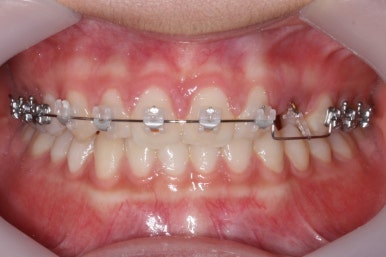

마무리 때의 사진입니다.

윗니만 부분교정하였지만 교합에도 이상 없이 매복되었던 송곳니는 매우 잘 위치를 잡았습니다.

송곳니 부위는 다시 틀어지지 않게 하기 위해 유지철사를 붙여주었습니다.

총 치료기간은 20개월 소요 되었습니다.

부산매복치아교정 상악 부분교정을 통해 매복치를 교정해준 이번 치료의 전후사진 비교입니다.

썩은 유치 대신 영구치 송곳니는 매우 자연스럽게 위치되었습니다. 아랫니는 교정하지 않았기 때문에 약간 삐뚠 느낌은 남아있지만 맞물림은 크게 문제가 없게 마무리 되었습니다.